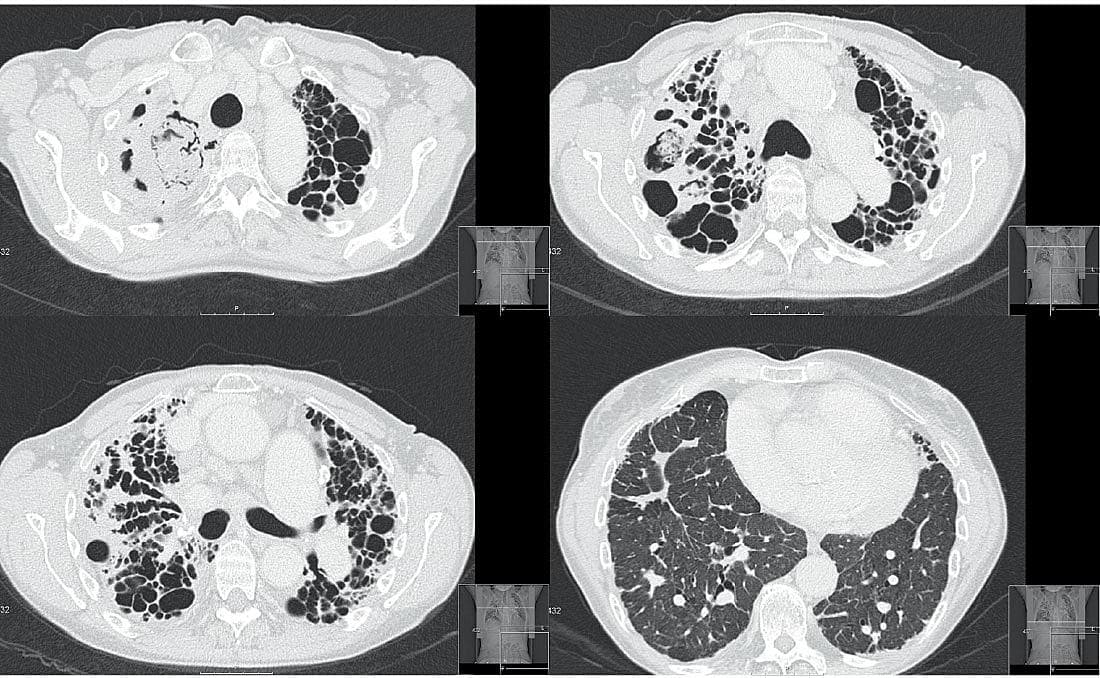

Der blev foretaget en CT af thorax hos en 64-årig kvinde, der havde haft sarkoidose gennem 20 år. Sygdommen blev initialt diagnosticeret ved lymfeknudebiopsi fra mediastinum, forhøjet niveau af S-angiotensinkonverterende enzym, radiologiske forandringer og udelukkelse af differentialdiagnoser.

Billedet viser snit fra fire niveauer, hvor man ser forandringer svarende til lungesygdom i sidste stadium. Apikalt ses der svære fibrotiske forandringer med »bikagetegning« og cystiske forandringer.

I mediastinum ses forstørrede glandler. Basalt ses lungevæv med mere normalt udseende.

Trods de meget svære forandringer var hendes ventilatoriske kapacitet relativt velbevaret med forceret eksspiratorisk volumen i første sekund (FEV1)

på 1,7 l og forceret vitalkapacitet (FVC) på 1,9 l svarende til henholdsvis 67% og 65% af forventet værdi. Ifølge Tiffeneauindex (FEV1/FVC) på 0,87 er der således tale om en restriktiv lungesygdom.